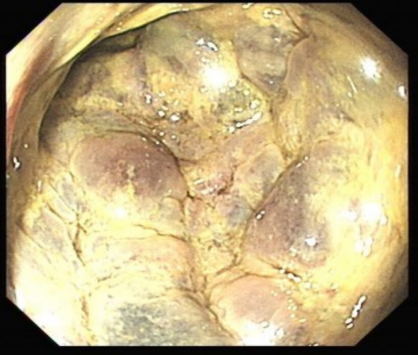

突如其来的腹痛、发热、寒战、黄疸近日,78岁的潘大爷讲述自己前些天毫无征兆突发腹部胀痛,伴有发烧、寒颤、恶心呕吐、胸闷、小便黄,实在忍不住,便...